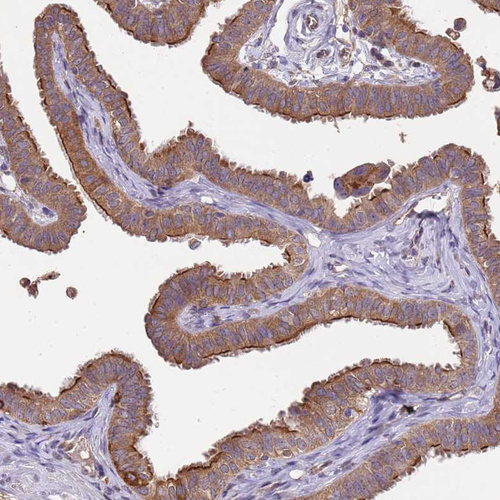

Immunohistochemical staining of human Fallopian tube shows moderate cytoplasmic positivity in glandular cells.